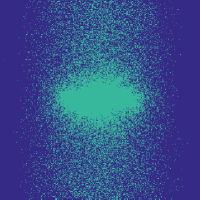

![]() |

Figure 6 (Left) illustrates that the learning-based approach outperforms the randomized variable-density approach. Note that here we use the function with , as introduced in Section II-D. We use Hadamard sampling, since it is easy to implement in digital hardware [28]. The density function of [3] is parametrized by the radius of fully sampled region, , and the polynomial degree, . We choose the parameters’ values that yield the lowest reconstruction error on the training set for each compression rate in the ranges and , taking the best realization over 20 random draws in each case.

Figure 6 (Left) shows example reconstructions at and compressions. A likely reason for the reduced error due to our approach is that we do not assume any shape for the distribution of the indices.